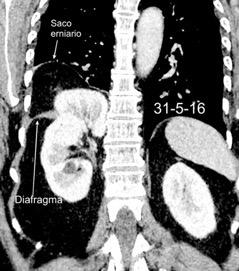

54. QUISTE HIDATÍDICO DIAFRAGMÁTICO

56. ROTURA DIAFRAGMÁTICA. TRAUMA